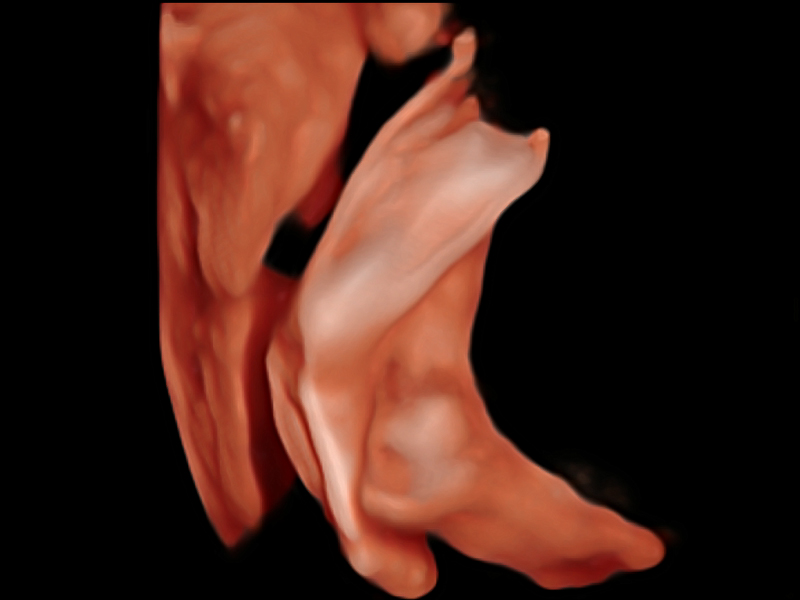

新一代微米成像技術(shù)大大提高了器官和病變的可見(jiàn)性。高清對(duì)比度分辨率將抑制斑點(diǎn)噪聲,同時(shí)保持真實(shí)的組織結(jié)構(gòu)。